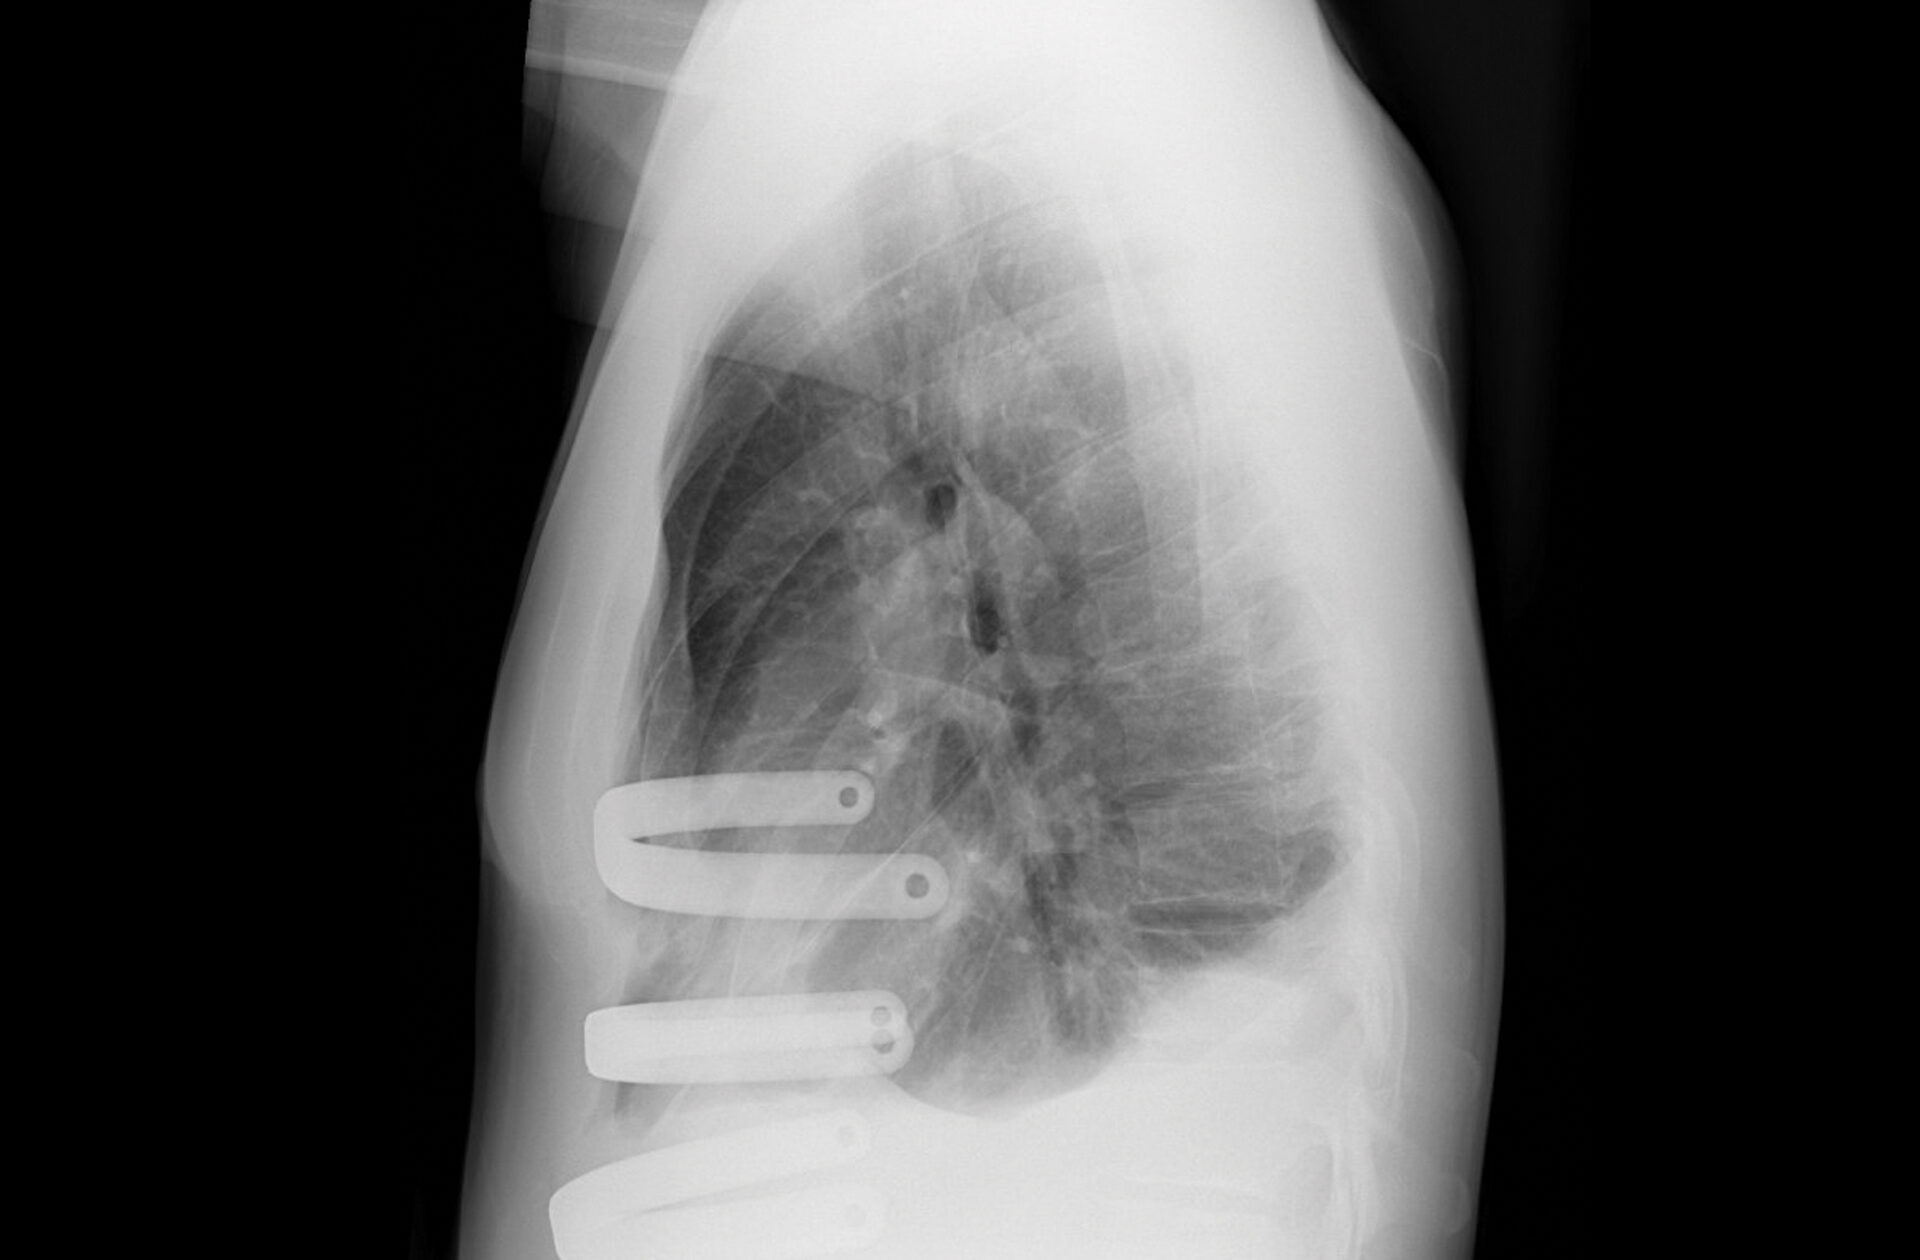

Preoperative chest CT of the patient’s pectus excavatum. Source: NYU Langone Health

The patient was reporting intermittent palpitations, chest pain, worsening shortness of breath with activity, and decreased exercise tolerance. “With a Haller Index of 6.5, the severity of the chest deformity was compressing the patient’s right atrium and ventricle, and limiting full lung expansion,” Dr. Bizekis says.

After carefully reviewing the patient’s chest CT imaging, he recommended the minimally invasive Nuss procedure.